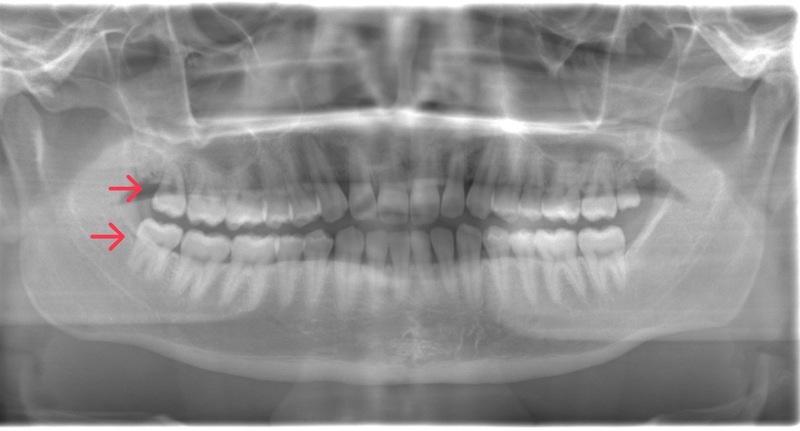

CASE 12

基本情報

| 年齢・性別 | 29歳・女性 |

| 主訴 | 右下の親知らず抜きたい |

| 抜歯期間 | 30分 |

| 抜歯費用 | 約2,500円(保険内) 別途CT撮影で3,000円 (2022年8月現在) |

| 抜歯内容 | 右下親知らずの半埋伏抜歯 |

| 治療方針 |

右下の親知らずが斜めにはえていて、頭が半分出ている状態です。このままでは食べものが挟まりやすく、歯ブラシで汚れを落とすことが難しいです。 虫歯や歯周病になりやすくなってしまうため抜歯を行いました。 親知らずが下顎神経と近いため、CTを撮影して確認してから抜歯を行いました。 |

| 特記事項 |

下顎神経が親知らずと近い場合、親知らず抜歯を2回に分ける場合があります。 まず1回目に歯冠だけを抜きます。 手前の歯でストッパーになっている部分を落とすことで、歯根が移動して神経から離れます。 1年程経過をみて、2回目の抜歯を行います。 |